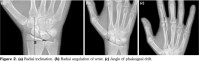

Anteroposterior radiography was performed on both hands of all patients by the same technician using the standard technique. Radial inclination (RI) is the angle between the distal surface and the longitudinal axis of the radius. The normal range of RI specified in the literature is 21° to 25°.[9] Radial angulation of the wrist (RAW) is the angle between the radial corner of the second metacarpal bone and the distal radius surface.[10] The angle of phalangeal drift (APD) is measured at the intersection of the lines along the shafts of the second metacarpal bone and the second proximal phalanx. As APD increases, the ulnar deviation of the fingers increases.[11] The radiographic measurements were repeated three times for each patient and averaged. The measurements of RI, RAW, and APD were shown in Figure 2.